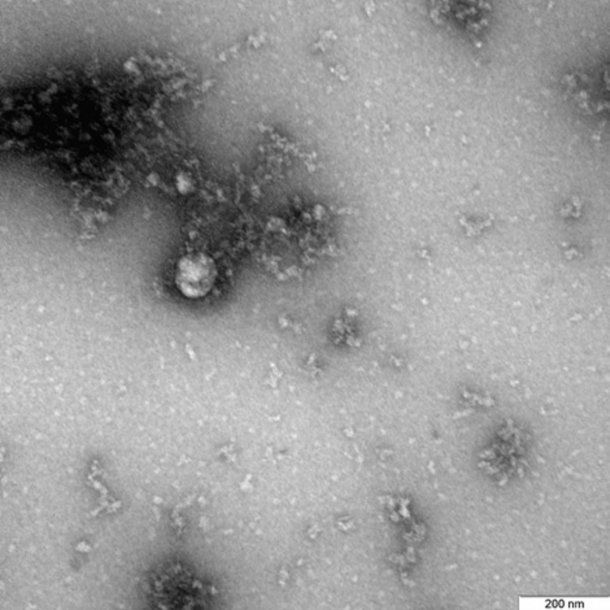

Rusia: lograron fotografiar la cepa británica del Covid-19

El Gobierno de Rusia anunció que pudo tomar la primera foto de la variante del Covid-19 detectada en el Reino Unido, que podría ser más mortal que la original.

El Servicio federal para la Supervisión de la Protección de los Derechos del Consumidor y el Bienestar Humano de Rusia (el Rospotrebnadzor) anunció este lunes que se logró tomar la primera foto de la variante del nuevo coronavirus que fue detectada por primera vez en Kent, sur del Reino Unido. Tras confirmarse que la "cepa británica" es más contagiosa que la que causó la primera ola de la pandemia de Covid-19, las autoridades de ese país sostienen que además podría ser más mortal.

Días después de que el Gobierno de Rusia anunciara que tiene una segunda vacuna contra el coronavirus casi lista, la EpiVacCorona, un equipo del centro de virología y biotecnología Véktor, donde se desarrolló esa fórmula, mostró la primera foto de la variante británica, que fue aislada de un paciente en diciembre de 2020.

"La fotografía del virus bajo el microscopio fue obtenida en el marco del estudio continuo de las características de esta variante del nuevo coronavirus, incluidas sus particularidades estructurales y manifestaciones en culturas celulares y modelos experimentales con el uso de animales de laboratorio", informó el Rospotrebnadzor en un mensaje reproducido por el sitio Actualidad RT.